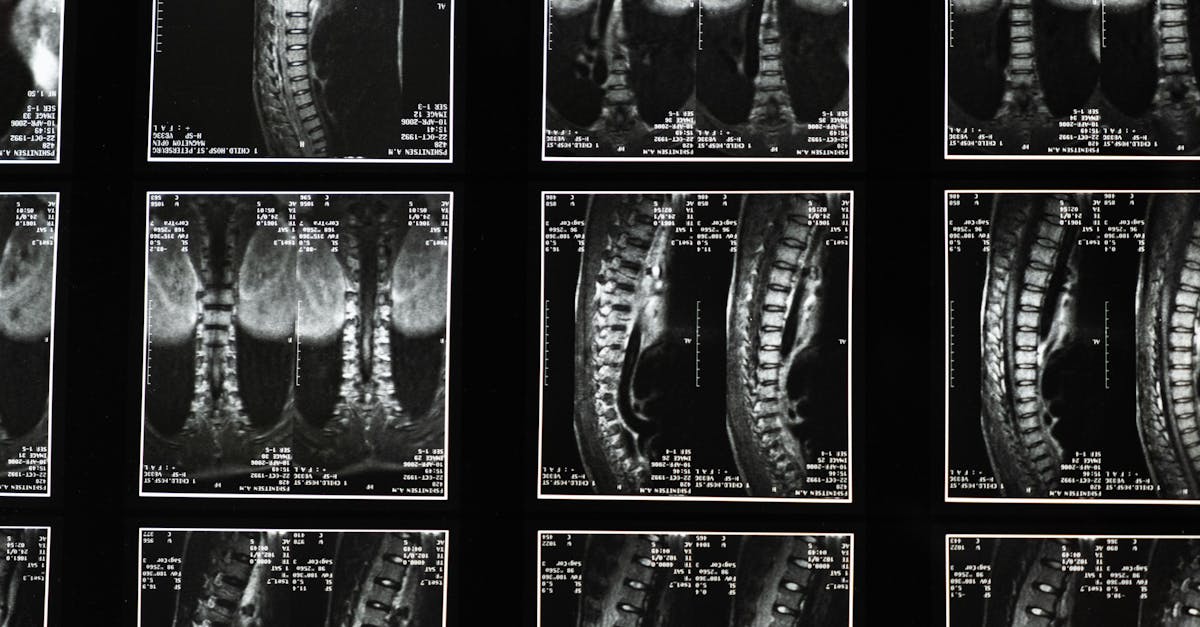

La décompression neurovertébrale utilise un équipement spécialisé qui applique une traction douce sur la colonne vertébrale. Ce processus crée un espace entre les vertèbres, ce qui réduit la pression exercée sur les disques et les nerfs. Les patients souffrant de douleurs aiguës, telles que les hernies discales ou la sténose spinale, peuvent bénéficier de ce traitement. La technique favorise également une meilleure circulation sanguine dans la région affectée, ce qui contribue à la guérison des tissus endommagés.

La décompression neurovertébrale est une méthode innovante et non invasive, idéale pour les patients souffrant de douleurs chroniques liées à la colonne vertébrale et qui hésitent face à des interventions chirurgicales. En appliquant une traction douce sur la colonne vertébrale, cette technique vise à réduire la pression sur les disques intervertébraux et les nerfs, favorisant ainsi une circulation sanguine améliorée et une régénération des tissus. Dans cet article, nous explorerons les avantages de cette méthode pour les patients, les indications appropriées, ainsi que le processus de traitement.

Le traitement se déroule généralement sur une série de séances, durant lesquelles le patient est installé confortablement sur une table spécialisée. Le praticien applique une traction douce et contrôlée sur la colonne vertébrale, permettant ainsi de créer un espace entre les vertèbres. Ce processus favorise la réduction immédiate de la douleur et construit un environnement favorable à la guérison.

La technologie utilisée dans la décompression neurovertébrale repose sur un principe simple et efficace : créer un espace entre les vertèbres. Cette méthode utilise un équipement spécialisé qui applique une traction douce et contrôlée sur la colonne vertébrale. En créant cet espace, la pression sur les disques intervertébraux et les nerfs est considérablement réduite, ce qui permet d’atténuer les douleurs et d’améliorer la circulation sanguine dans la région affectée. La décompression favorise également une meilleure régénération des tissus, contribuant ainsi à un processus de guérison optimal.